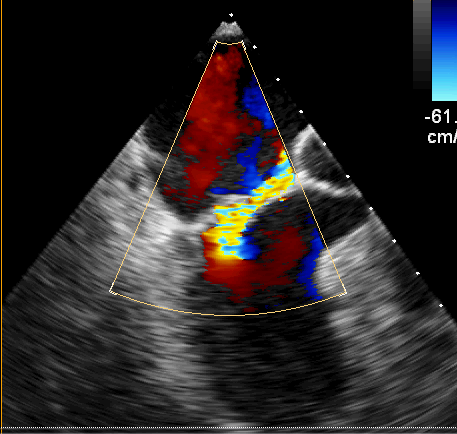

术前超声

经过积极完善术前检查,心脏超声提示二尖瓣后叶脱垂(P2区),偏心反流(3+—4+级),三尖瓣少量反流,目前最严重的就是二尖瓣这扇“门”,如果不及时处理,患者很快就会出现心衰,甚至危及生命,考虑患者高龄,同时不愿接受人工瓣膜置换,高峰主任团队经过缜密的研究和充分的评估,认为患者有微创手术瓣膜成形的条件,可以通过该术式解决这个大难题。相较于瓣膜置换术,瓣膜成形对主刀医生在术中的精细操作与精准判断提出更高的要求;而微创手术,减少了术中的牵拉和损伤,术后胸骨完整性得以保留,具有创伤小、出血少、恢复快,对术后美观和呼吸功能具有显著优势。在兄弟科室的密切配合下,仅用3个多小时,高峰主任团队通过右侧肋间一个5厘米的小口子,成功对损坏的二尖瓣进行了修复重建,心脏复跳后复查心脏超声,二尖瓣微量返流,手术效果满意。患者安返心外科监护室,在医护人员的精心照护下,患者恢复良好,第二日转回普通病房进一步康复治疗。